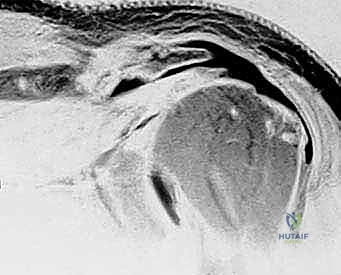

- MRI: This is indispensable for evaluating the rotator cuff, biceps tendon, labral, and capsular pathology. We assess the size of the tear, especially subscapularis and infraspinatus involvement, the distance of tendon retraction from the greater tuberosity, and critically, the extent of fatty degeneration in the involved muscle bellies. These changes, often irreversible, lead to decreased tendon excursion and tissue compliance.